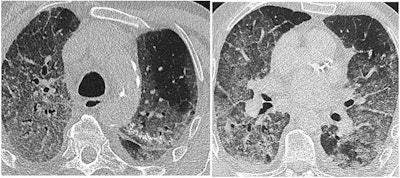

SARS-CoV-2 appears to be transmitted primarily through respiratory droplets, with a five-day median timeframe between exposure and symptoms. Thoracic CT has proven to be highly sensitive for confirming SARS-CoV-2 infection, with some studies reporting values as high as 97%, and it offers quicker results than reverse transcription polymerase chain reaction (RT-PCR) testing, according to Revel.

Revel also noted the risk of cytokine release syndrome in some patients, as well as a risk of pulmonary embolism in some patients (between 23% and 30% of those admitted to the intensive care unit with elevated D-dimer values), she told session attendees. Yet other SARS-CoV-2-infected patients develop microvascular injury syndrome involving at least the lungs and skin, which explains "why COVID-19 has clinical features distinct from typical ARDS [acute respiratory distress syndrome] with profound hypoexemia contrasting with relatively well-preserved lung mechanics," she said.